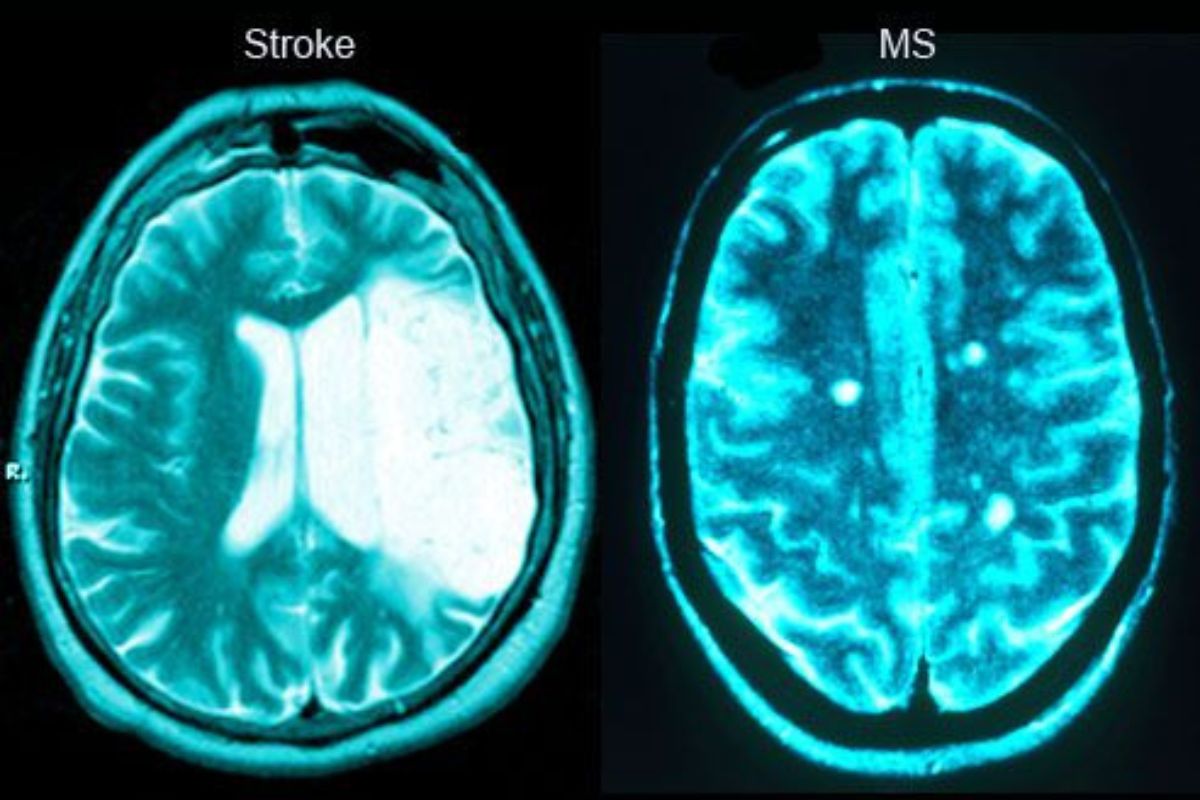

Bell’s Palsy affects only the face, while stroke often involves weakness in limbs, speech difficulties, and reduced consciousness. Proper diagnosis by a neurologist is essential.

Diagnosis is based on clinical examination. Additional tests like MRI or CT scan may be performed to rule out other conditions.